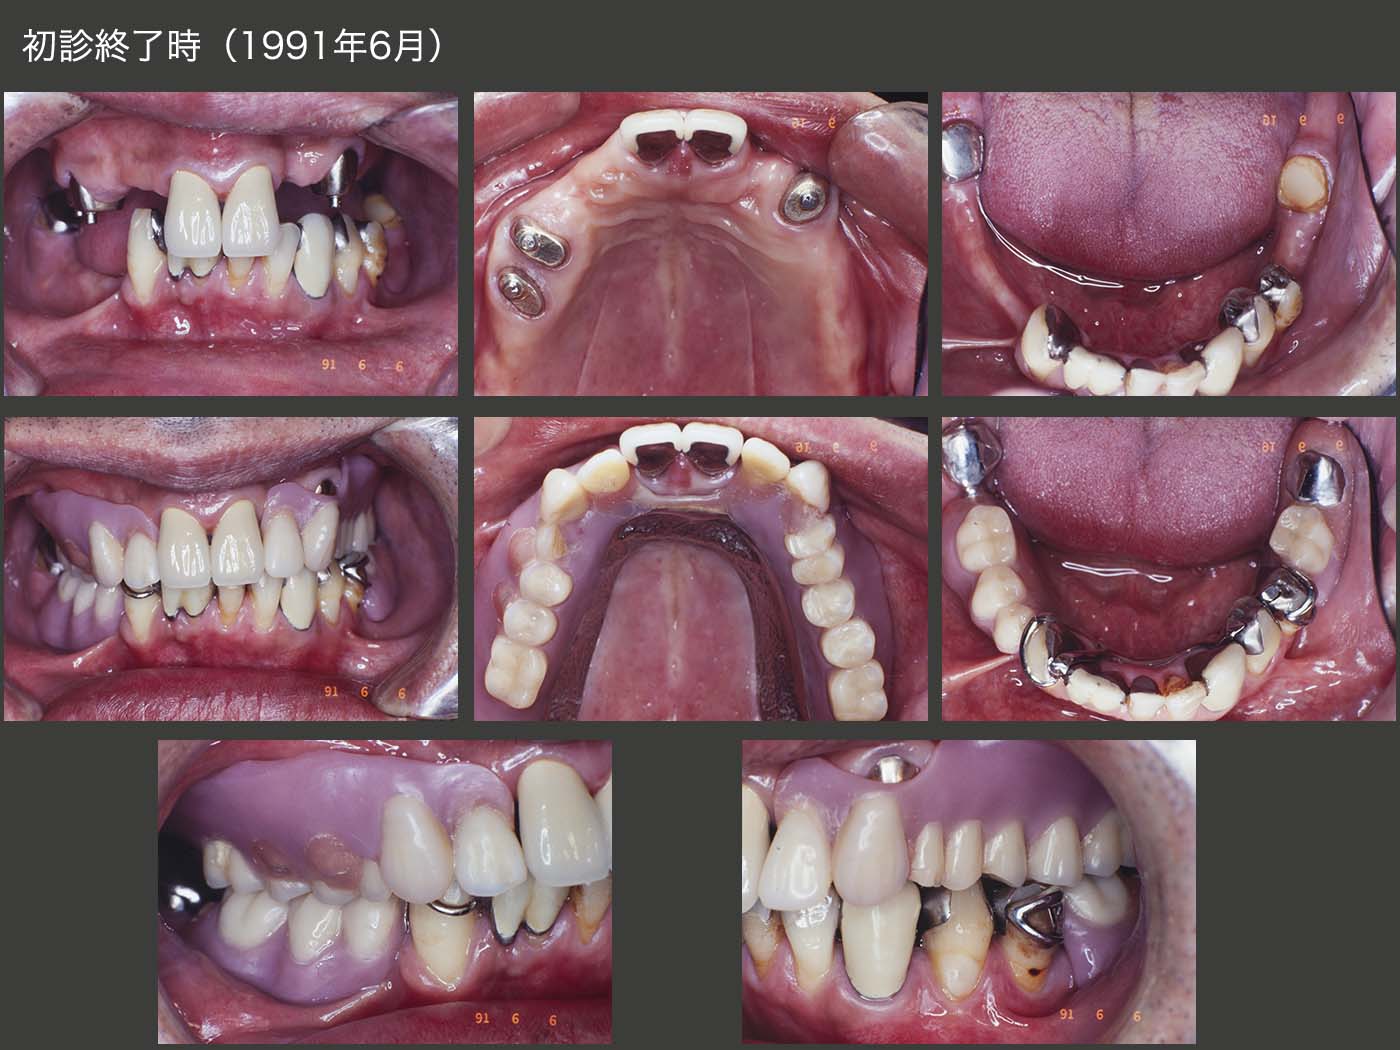

1991年6月,初診終了時の状態.今の自分の技量ならば,上顎のアタッチメントを装着した支台歯については,歯冠長延長術を行ったうえで,クラウンを装着しクラスプ義歯にするか,あるいはコーヌス義歯にすると思われる.しかしこの当時は,外科手術を行わずに手短に装着できる,根面アタッチメントを応用した義歯を装着することが多々あった.この症例も,治療期間を短縮したいがためにアタッチメント(Baer stepped anchor)を使用してしまった.また,上顎アタッチメントを義歯床で被覆してしまい,辺縁歯肉の開放を行わなかった.